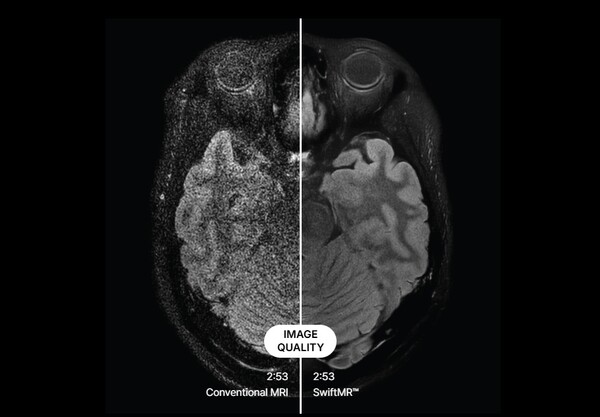

전통적인 MRI 촬영 영상(왼쪽)과 SwiftMR로 노이즈를 제거한 영상(오른쪽) 비교. /에어스메디컬

에어스메디컬의 기술 원리는 MRI의 물리학적 특성을 깊이 이해하는 데서 출발한다. MRI는 촬영 부위에 자기장을 적용해 수소 원자의 진동에서 나오는 파동들을 합쳐 시그널을 만들어내는 방식이다. 충분한 시그널을 얻어야 노이즈가 발생하지 않는데, 에어스메디컬은 시그널을 덜 얻었을 때 발생할 수 있는 수만 가지 노이즈 패턴을 2~3년간 딥러닝으로 학습시켜 어떤 패턴이 나와도 이를 제거할 수 있는 모델을 완성했다.